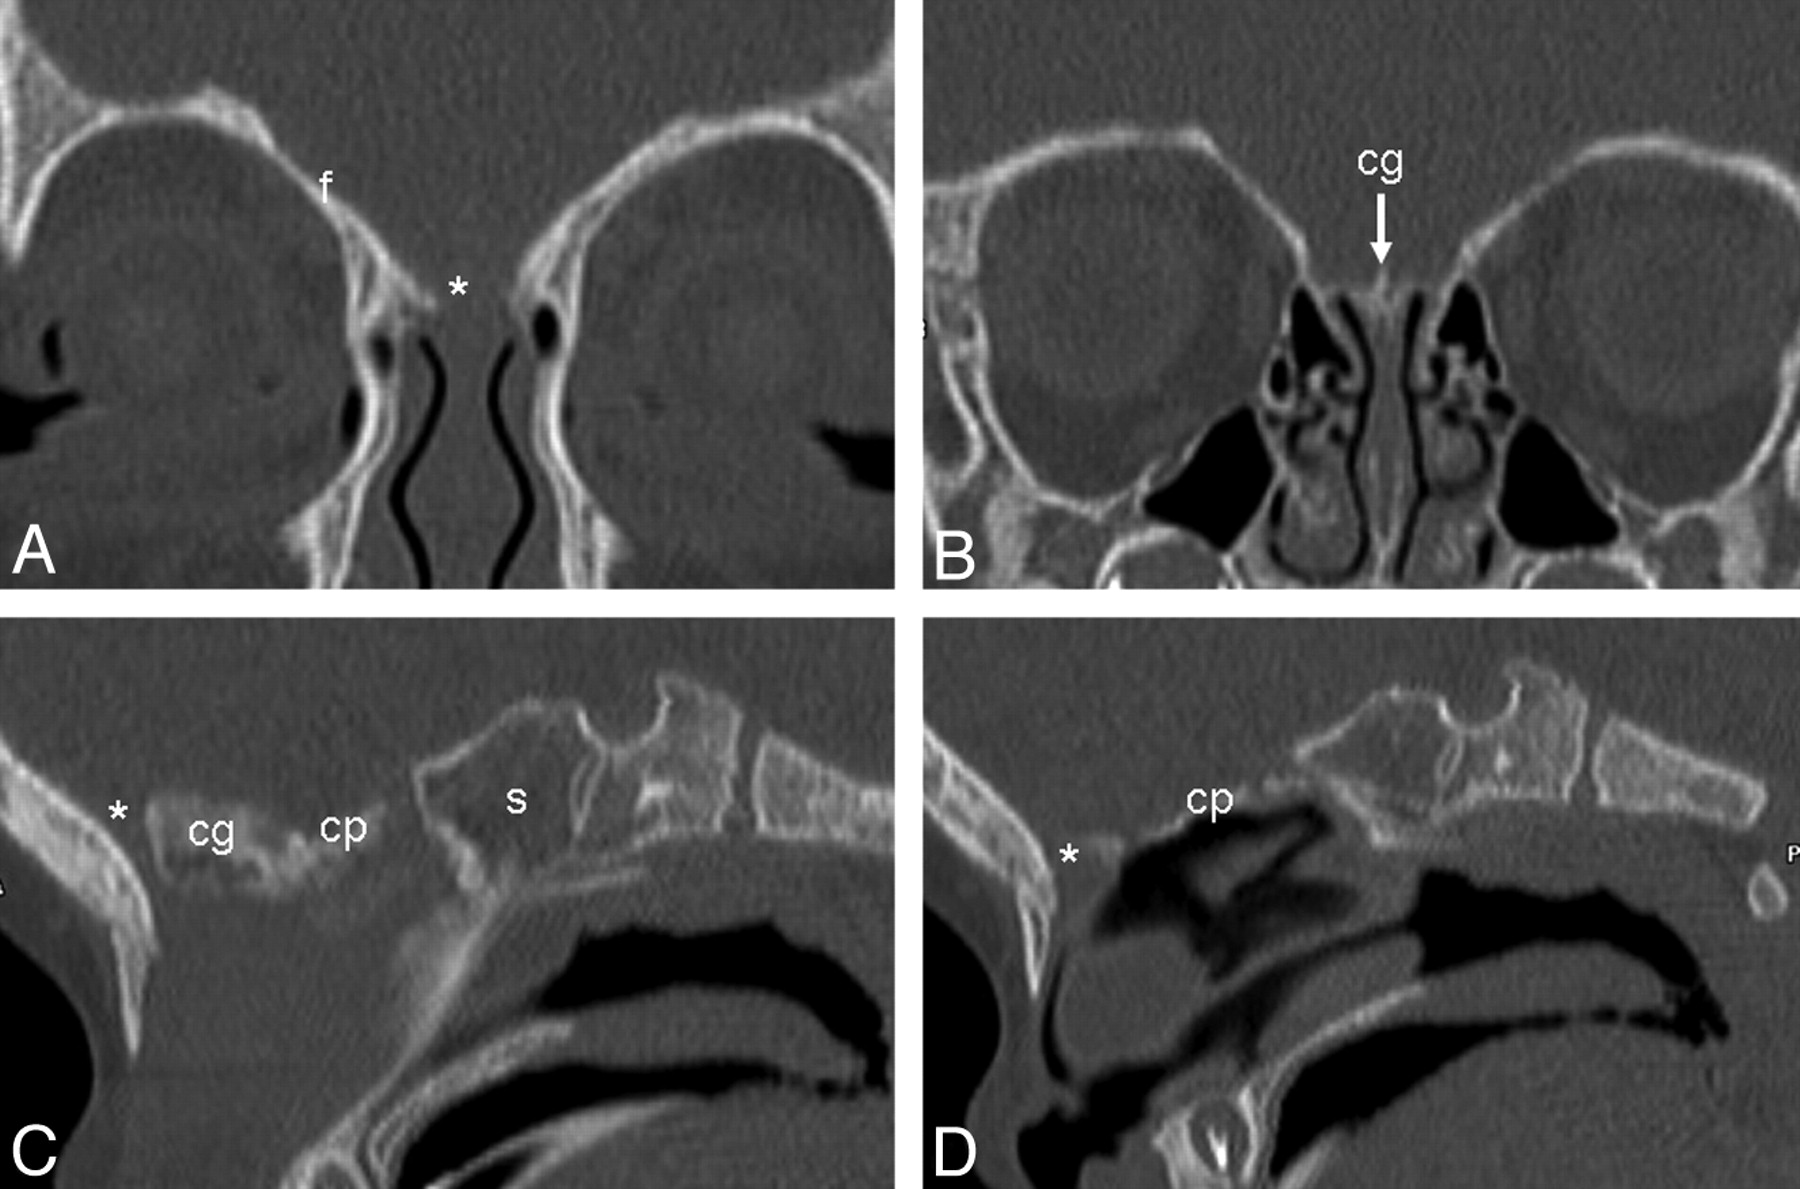

Age 4 years 7 months. Anterior (A) and posterior (B) coronal, midline (C), and parasagittal (D) images show complete ossification of the anterior skull base with typical well-corticated margins of the foramen cecum.

Age, 9 months. Anterior (A) and posterior (B) coronal, midline (C), and parasagittal (D) images show that ossification is more complete posteriorly than anteriorly, with ossification of the cribriform plate extending laterally to the frontal bones. There is a persistent unossified portion anteriorly (asterisk).

Age, 3 years 3 months. Anterior (A) and posterior (B) coronal, midline (C), and parasagittal (D) images show progressive ossification of the cribriform plate posteriorly, with only a small persistent unossified portion of the skull base anteriorly (arrow).